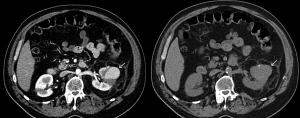

45-Year-Old Female With Gross Hematuria Post Partial NephrectomyByBrian Morse, MD,Kevin ShahbazianMarch 1st 2018A 45-year-old female presents with gross hematuria 5 days after a laparoscopic partial nephrectomy for renal cell cancer. What is your diagnosis?